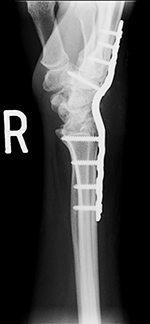

Plates continued...

Buttress plates are used more for bony alignment rather than compression. They are indicated for situations in which the fracture fragments are unstable in compression or axial loading. They are most commonly found in the distal radius and in the proximal tibia where they stabilize tibial plateau fractures (figure: buttress plate with bone substitute; figure tibia buttress plate). They are also sometimes found in distal femur intercondylar fractures (figure: femur buttress plate).

Plates

are most commonly used for fixation of long

bones, but they also are used in the spine and for

arthrodesis of the wrist (figure: wrist arthrodesis) (Ruedi, 2007; Benjamin, 1994). When diaphyseal fractures in the long